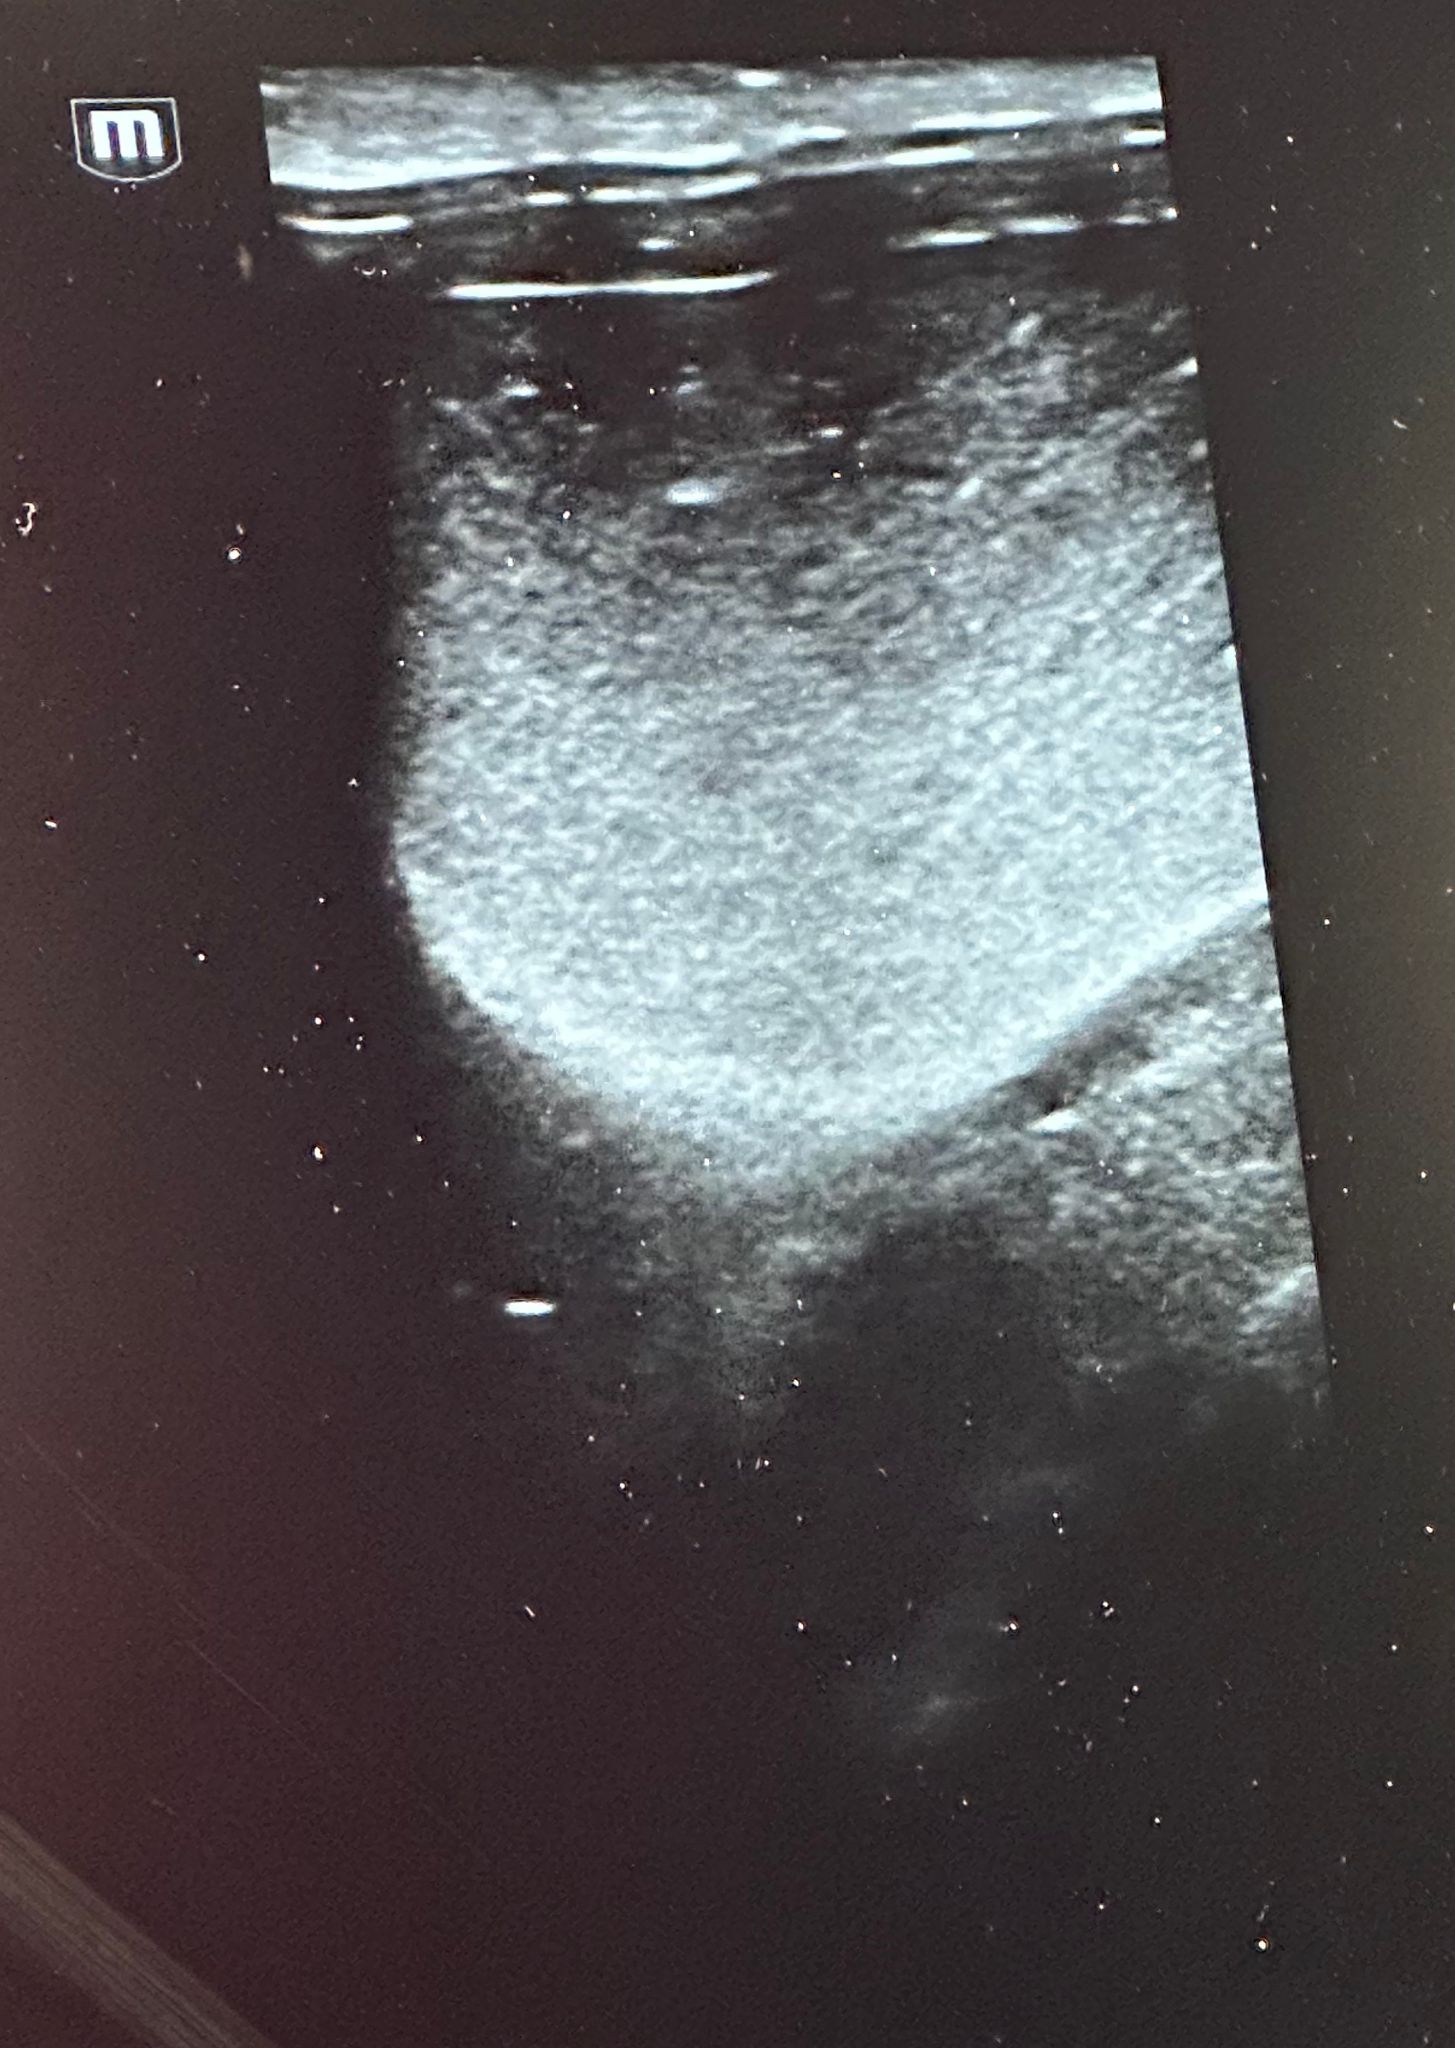

Weiterführende Untersuchungen: Ultraschall

- rektale Ultraschalluntersuchung der Blase

- auffälliges, abgesunkenes Sediment in der Harnblase/am Harnblasenhals

- ggr. Verdickung der Blasenwand